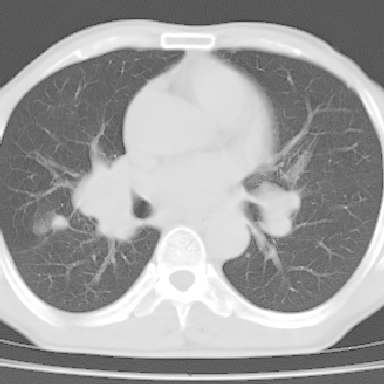

以下是引用zjzjr在2007-3-23 17:24:00的发言:[br]双侧肺门淋巴结明显肿大,以左侧为著,支气管受压变窄,肺内可见结节状及絮状高密度影,边缘模糊.考虑淋巴瘤肺内浸润.